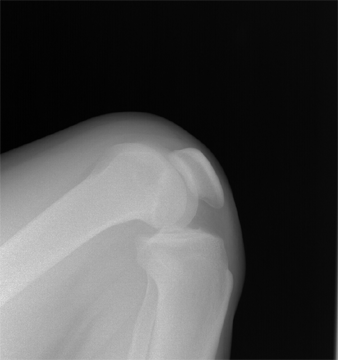

●当出现这种问题时,就意味着我们的身体正在向我们发出警告,需要去医院进行膝关节X光检查和膝关节MRI检查。

当关节处的软骨磨损后,我们的身体就会发现关节不再能像以前那样承受那么大的压力,关节也不再像以前那样稳定。所以当软骨磨损时,我们的身体就会想要寻找一些朋友。来帮忙,那么这些帮助结构就是骨赘,也就是我们常听到的骨质增生或者骨刺。通过X线检查,我们可以了解骨刺的数量以及关节间隙是否有明显的变窄,这对判断骨关节的状况非常有帮助。

但在骨关节炎的早期阶段,往往形成的骨赘并不多,关节间隙也不会变窄。那么此时如何判断接头处的情况呢? MRI 是最好的选择。通过MRI,我们可以发现关节内的软骨是否磨损,关节腔内是否有少量液体,关节内骨头之间的压力是否发生变化!